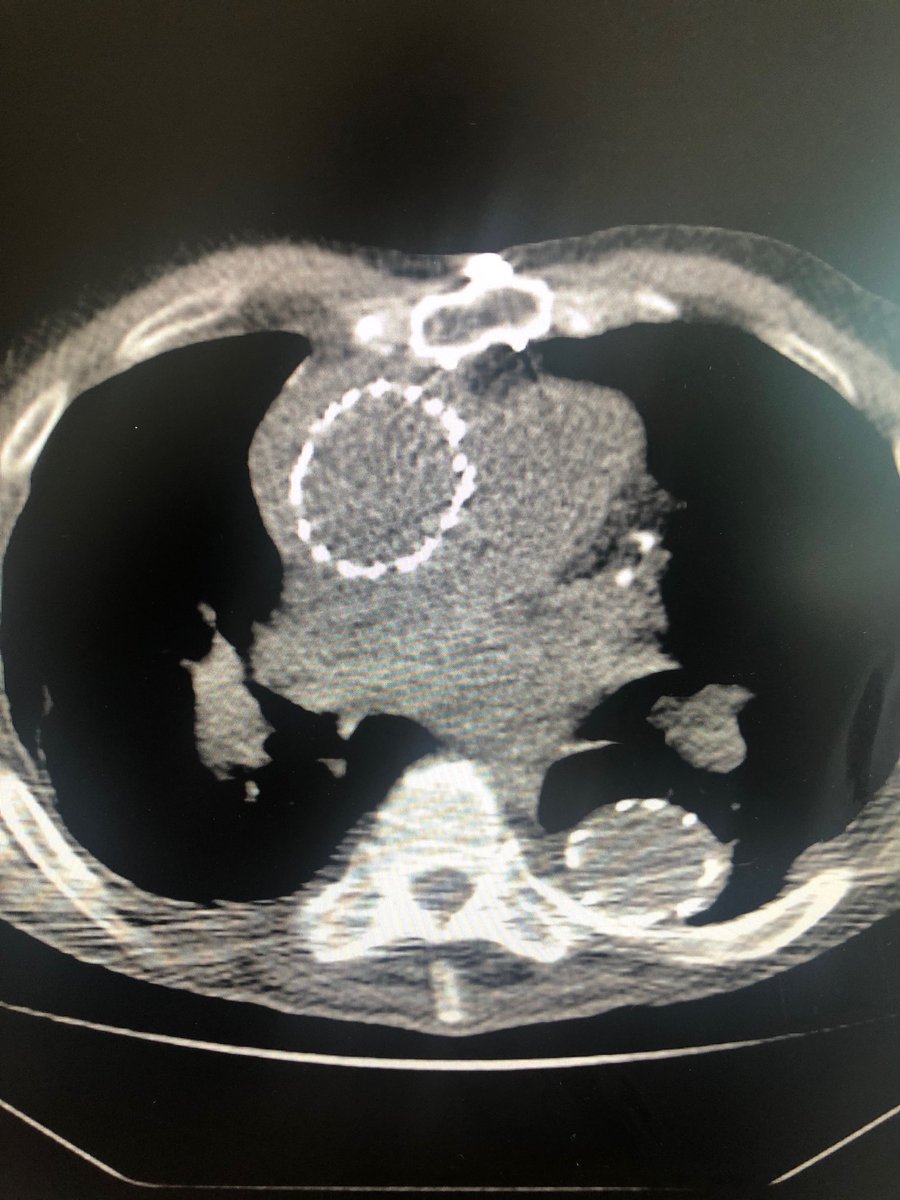

@DrAliAzizzadeh @CedarsSinai Beautiful 1 year follow up in a prohibitive risk patient with a commercially available device. Great work. Thank you for leading the way.

Emergency #TEVAR for #ruptured #typeA #dissection and #aneurysm in #nonagenarian. 1 year follow up #CT shows #healed #aorta #VascularSurgery @CedarsSinai